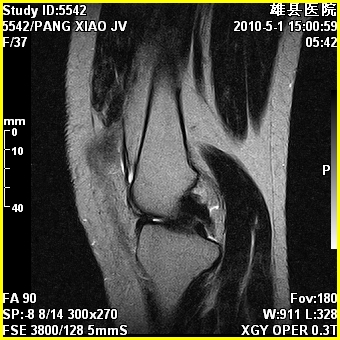

标题: MRI2894:患者右膝关节疼痛两月余,无明显外伤史 [打印本页]

标题: MRI2894:患者右膝关节疼痛两月余,无明显外伤史

右股骨下端前内侧类圆形异常信号,位于干骺端,呈长t1长t2改变,但信号不均,t1图上病灶中心见小片状稍高信号影,t2图上见散在稍低信号影,stir像呈高信号,因病灶较小,缺乏特征性改变,结合患者年龄及部位,考虑嗜酸性肉芽肿可能性大。胫骨关节面下的小囊状异常信号,如果一元论考虑则为嗜酸性肉芽肿,不过发生在这个部位的少见,二元论考虑为邻关节骨囊肿。半月板与前后交叉韧带均未见异常。

右股骨下端前内侧干骺端囊性良性病变,考虑 1内生软骨瘤 2骨囊肿 3肉芽肿。